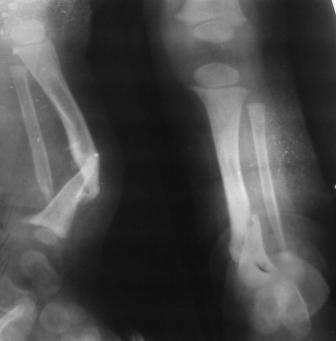

Глубокоуважаемые коллеги женщины! Поздравляем с праздником ВЕСНЫ, Международным женским днем - 8- МАРТА, здоровья , благополучия и успехов во всем! Ребенок 1г, мальчик, от первой беременности, родился без патологии весом 4кг, родители травму исключают, постепенно заметили деформацию н/з голени, которая начала увеличиваться . Брак родственный. Об-но; имеется угловая деформация открытым углом кзади на уровне н/з голени, ригидная , коррекции поддается мало. Функция коленного и г/с суставов не нарушены. Уважаемые детские ортопеды! Почему такое упорное молчание ортопедов! Я искреннее прошу прошения , если можно , мы нуждаемся в Ваших советах! План лечения; этапное, дистракционный аппарат, коррекция деформации, остеотомия в/з б/б кости, удлиняющая дистракция в обл остеотомии с одновременной компрессией в обл псевдоартроза и наблюдение , дальше по обстоятельству Вопросы; . 1. В каком возрасте можно начинать лечение, какие еще варианты лечения? 2. На Р-грамме как будто имеется недоразвитие дистального эпиметафиза м/берцовой кости, тогда что можно делать? С уважением Абдурашид.